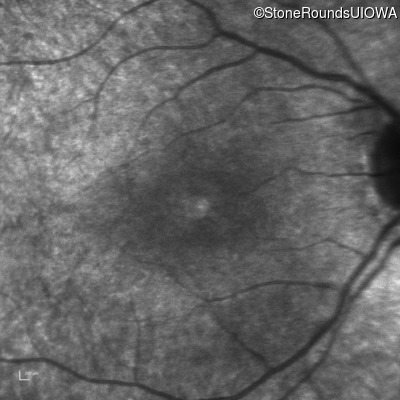

Infrared Fundus Photograph - Right - 20/25 -2

Exemplar